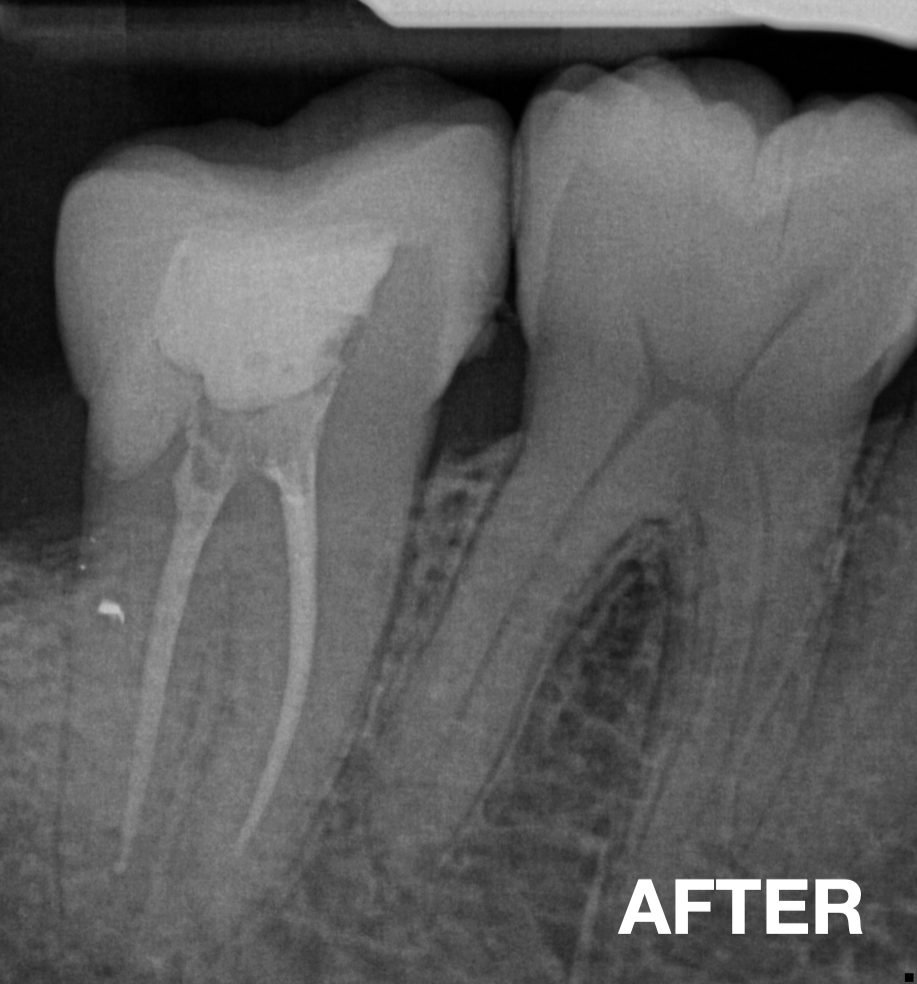

Before & After

📸 Before: missing tooth / fractured tooth

📸 After: restored tooth with natural-looking FRC